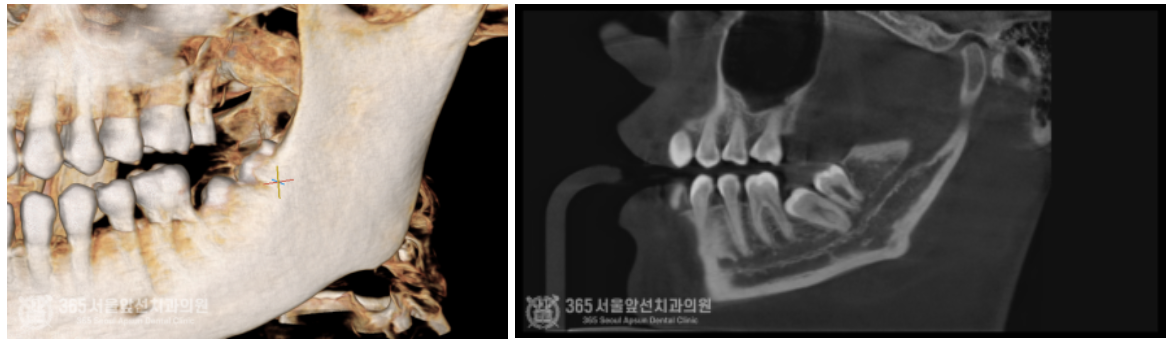

안녕하세요. 주안동치과 365서울앞선치과의원입니다. 오늘은 심각하게 매복된 사랑니 발치에 대한 치료증례를 살펴보겠습니다. 동네 치과에 가셨는데 신경과 거리도 너무 가깝고 매복도가 심해서 대학병원에 내원하셔서 발치하도록 권유받았다는 환자분께서 오셨습니다. 일단 엑스레이와 CT를 찍고 진단을 해봅니다 ㅎㅎ 환자분께서 너무 걱정하시더라구요. 걱정마세요. 어떤 사랑니도 자신있습니다 !! 촬영일시 : 2024.06.03. 처음 내원 당시 사진입니다. 어금니와 사랑니가 꼬여있고 매복되어있네요 ㅠㅠ 안전하고 신속한 발치를 위해서 CT까지 찍습니다. 촬영일시 : 2024.06.03. CT 입니다. 사랑니가 혀쪽으로 매복되어있고 신경관에 뿌리가 박혀있군요. 자 이제 발치를 시작해봅니다 ㅎㅎ 안전하고 신속하게 빼드렸습니다 ㅎㅎ 촬영일시 : 2024.06.03 발치된 치아들이구요. 매복발치이기에 치아를 분할하여 발치하였습니다. 촬영일시 : 2024.06.03 발치 후 엑스레이 사진입니다. 발치된 자리가 선명하게 보이네요 ㅎㅎ 안전하고 신속한 발치를 추구하는 치과의사 강동우였습니다. 더 좋은 치료증례로 찾아뵙겠습니다! [ 치료기간 : 치료기간: 2024년 6월3일 ] ※ 365서울앞선치과의원의 모든 포스팅은 각 진료과 의료진이 직접 작성합니다. 365서울앞선치과의원 블로그의 임상 케이스 게시물은 환자분께 의학적으로 정확하고 상세한 정보를 드리기 위해 각 진료과 의료진이 직접 작성하며, 모든 증례 사진은 본원 의료진이 직접 시술한 증례를 촬영한 것으로, 의료법 제23조, 제56조에 의거하며 환자분의 동의를 얻어 포스팅에 사용하였습니다. 또한 해당 케이스는 본 환자분의 치료 결과이며, 환자 상태에 따라 치료의 결과는 달라질 수 있습니다. |